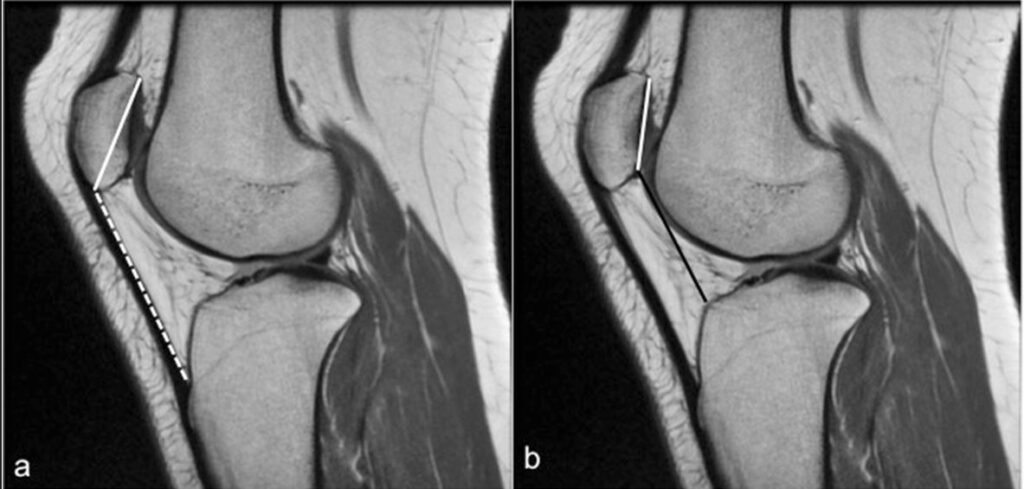

This article sets out to discuss the clinical and radiologic evaluation of patellar maltracking, offer an update on the cross-sectional imaging assessment, and summarize the management options.